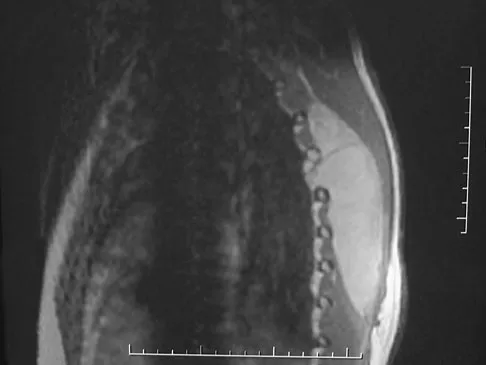

A 64-year-old man has had increasing pain in the left hip for the past 6 months. A radiograph and MRI scan are shown in Figures 25a and 25b. Biopsy specimens are shown in Figures 25c and 25d. What is the recommended treatment?

A 38-year-old man has an enlarging left paraspinal soft-tissue mass. Based on the MRI scans and biopsy specimens shown in Figures 32a through 32e, what is the most likely diagnosis?